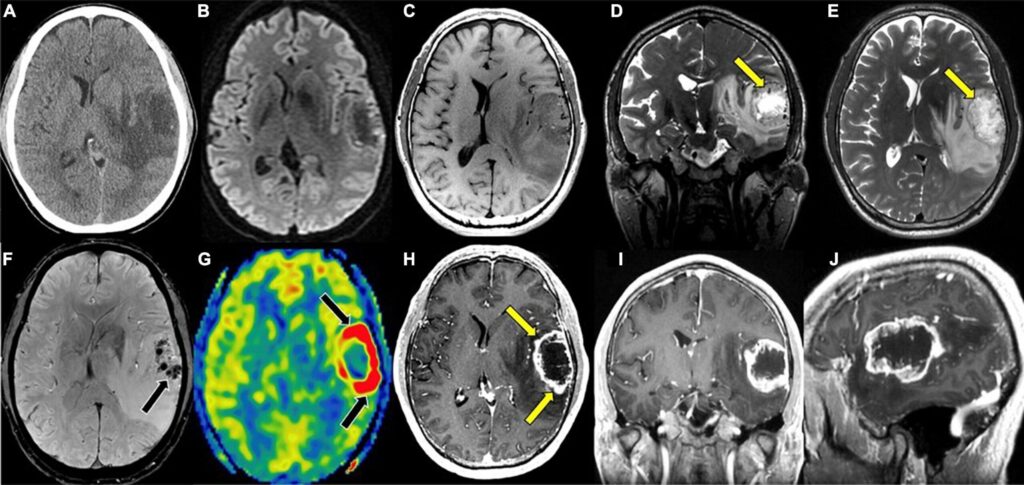

Contrast Material Some brain MRIs require contrast dye injected through an IV. This helps highlight certain brain structures and abnormalities. The contrast material used in MRI (gadolinium) is different from CT scan contrast and generally causes fewer allergic reactions.

Standard Brain MRI This basic scan provides detailed images of brain structure and can detect tumors, strokes, and other abnormalities.

MRI with Contrast Gadolinium contrast helps highlight blood vessels and certain types of brain lesions. The contrast is injected through an IV during the scan.